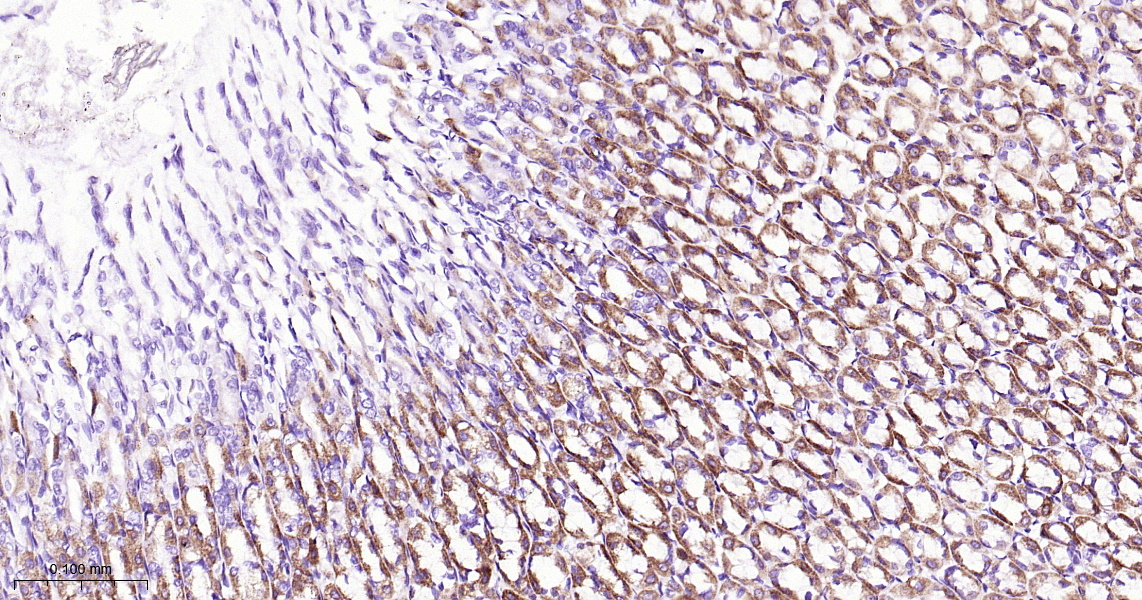

• IHC-P

IHC-P IHC-P1:50-200